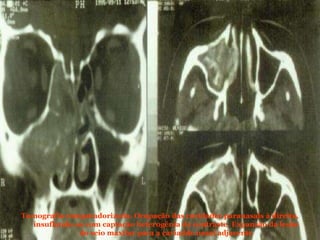

Tomografia computadorizada. Ocupação das cavidades paranasais à direita, insuflando-as com captação heterogênia de contraste. Expansão da lesão do seio maxilar para a caviadde nasal adjacente

Tomografia computadorizada. Ocupaçãodas cavidades paranasais à direita, insuflando-as com captação heterogênia de contraste. Expansão da lesão do seio maxilar para a caviadde nasal adjacente